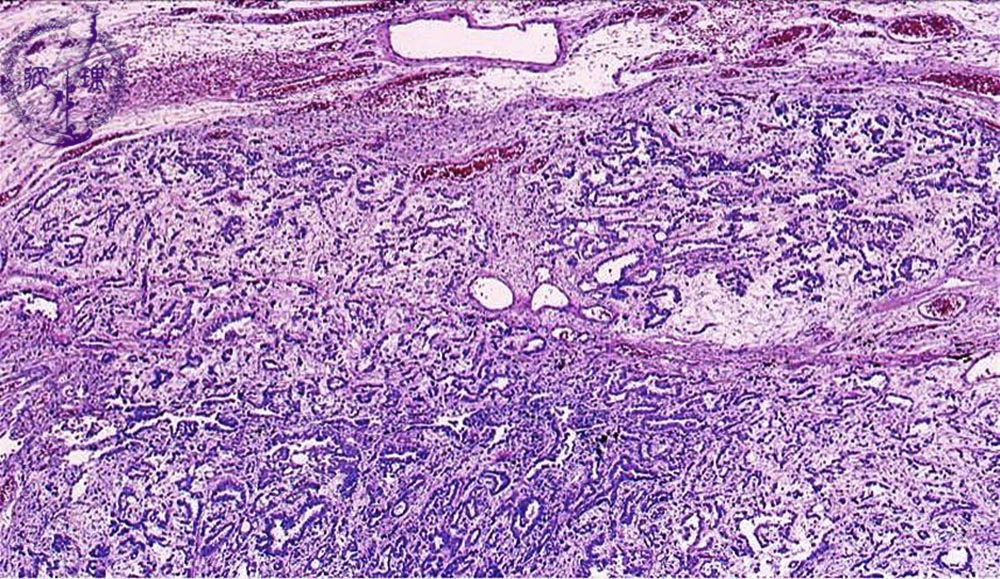

胸膜中皮腫ミクロ像(HE弱拡大)

ミクロ像(HE弱拡大):腫瘍は豊富な間質を有し、不規則な管腔あるいは偽乳頭を形成しながら浸潤性に増殖している。